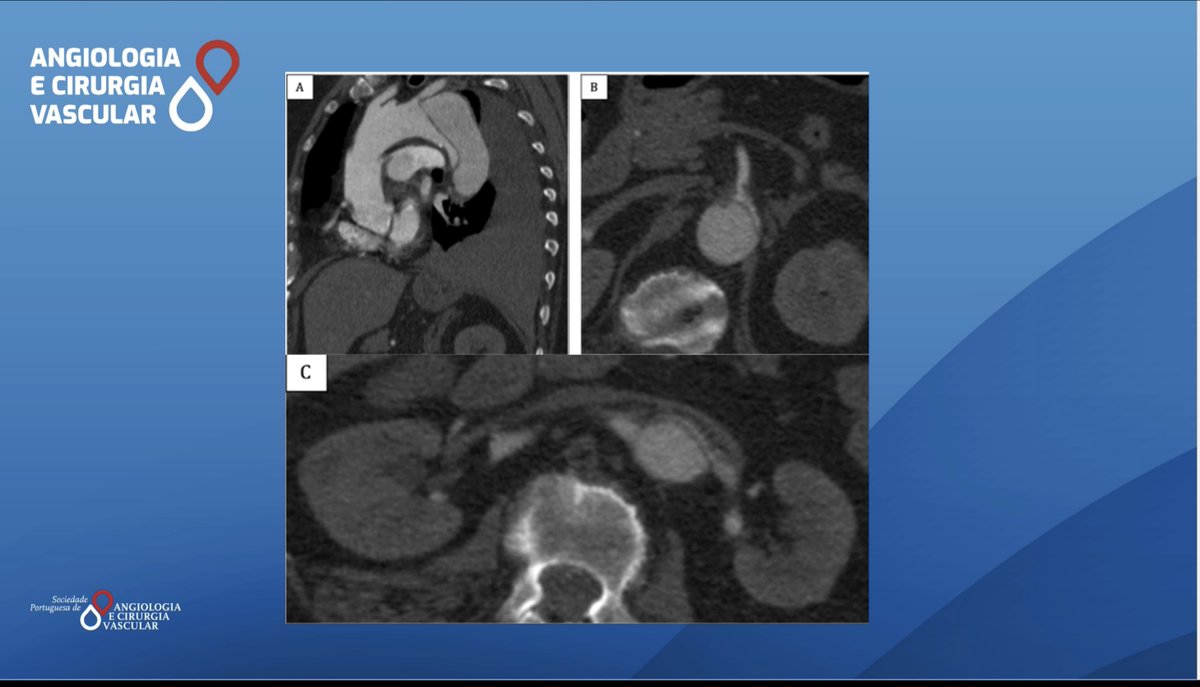

Mendes D. et al performed a parallel graft thechnique for a zone 6 aortic pseudoaneurysm. You can read more here lnkd.in/dPwgs6N8 #SPACV #Vascularsurgery ESVS European Vascular Surgeons in Training (EVST) Society for Vascular Surgery Vascular News

Here you can find the Endovascular solution chosen by Tavares C. et al acvjournal.com/index.php/acv/… #SPACV #Vascularsurgery #TypeBAcuteAorticDissection #TEVAR #PETICOAT European Vascular Surgeons in Training (EVST) ESVS Society for Vascular Surgery Vascular News